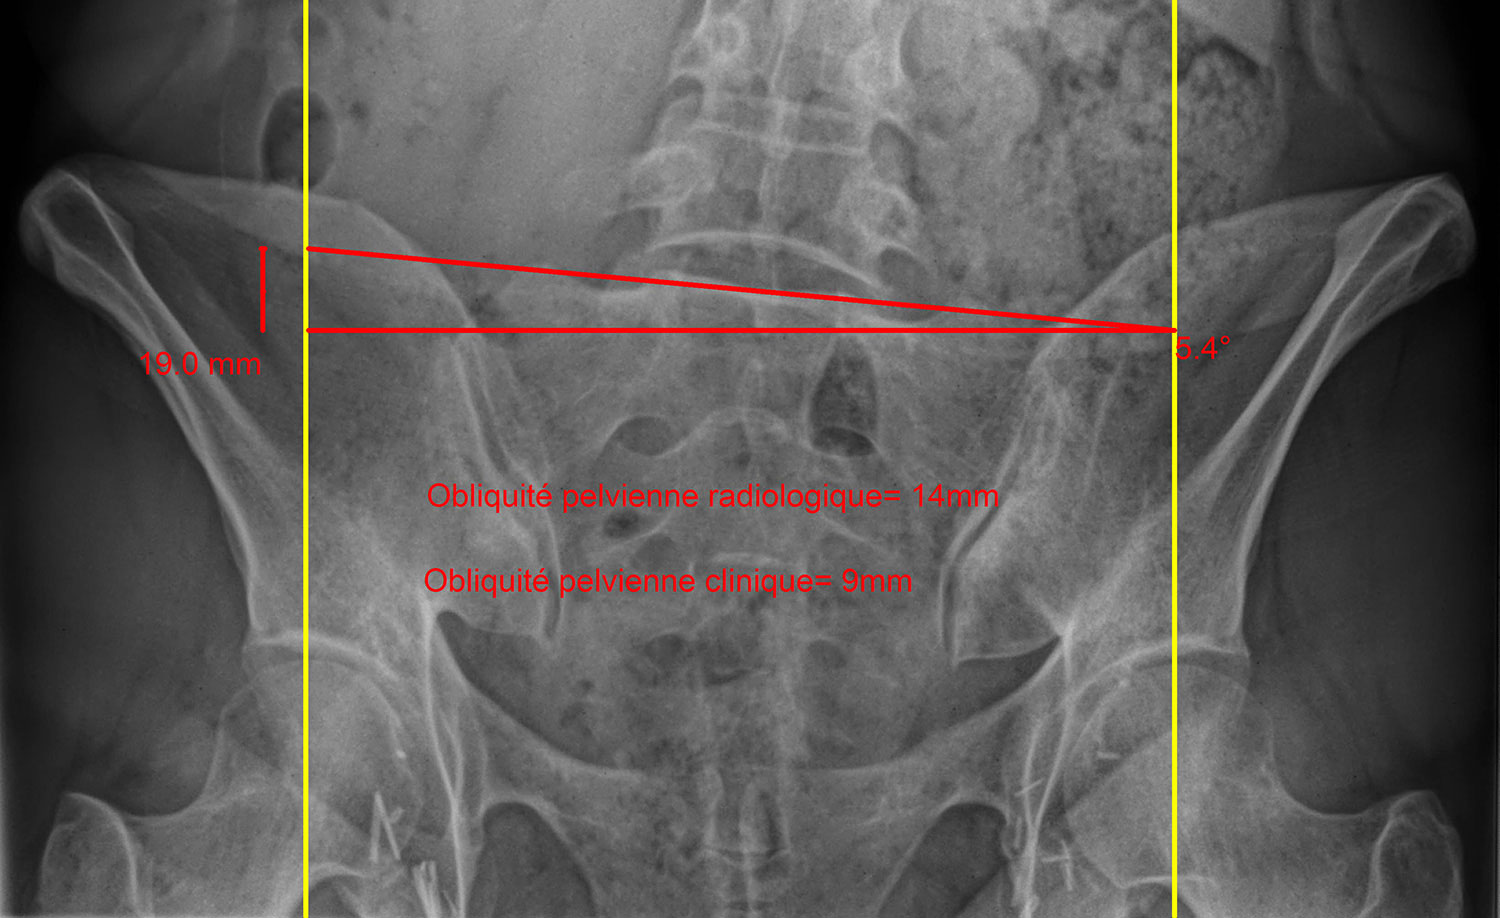

This makes it quite difficult to assess whether the pelvic inclination is due to an actual difference in leg length or to a postural problem or an intrinsic pelvic deformation. Only an experienced physician accustomed to the study of this type of phenomena and having specialized x-rays in hand can correctly diagnose the situation.

The method advocated by OrthoChiro chiropractors combines clinical (patient physical examination and muscular testing) and radiological assessments. First, we perform a visual appraisal of the patient’s overall posture including the pelvic area, then we observe their gait to identify any functional problems. Since an x-ray is only a 2D image of a 3D patient, it must always be interpreted with caution, which is why we save it for last and use it only to validate clinical observations.

Our method of radiological assessment of the pelvis is adapted from the Ferguson method, which according to our experience is much more clinically useful than a CT scan of the lower limbs. The 30° incline of the x-ray tube over a patient in frontal view allows for the simultaneous assessment of:

- hip height (femoral heads)

- pelvic bone (iliac) alignment

- disc inclination at the base of the sacrum—cornerstone that supports the spinal column and the entire weight of a person’s torso within their pelvis, transmitting it to the lower limbs. Because the sacroiliac joint barely moves at all (2° on each side), measurement in the coronal plane of disc L5-S1 inclination is therefore very representative of the mechanical constraints applied on the lower lumbar spinal column, provided, of course, that the x-ray be properly centred.

- lower lumbar spine alignment (L3-L4-L5) and potential compensations—it is crucial to take these into consideration so as not to undermine the patient should a shoe lift be considered.